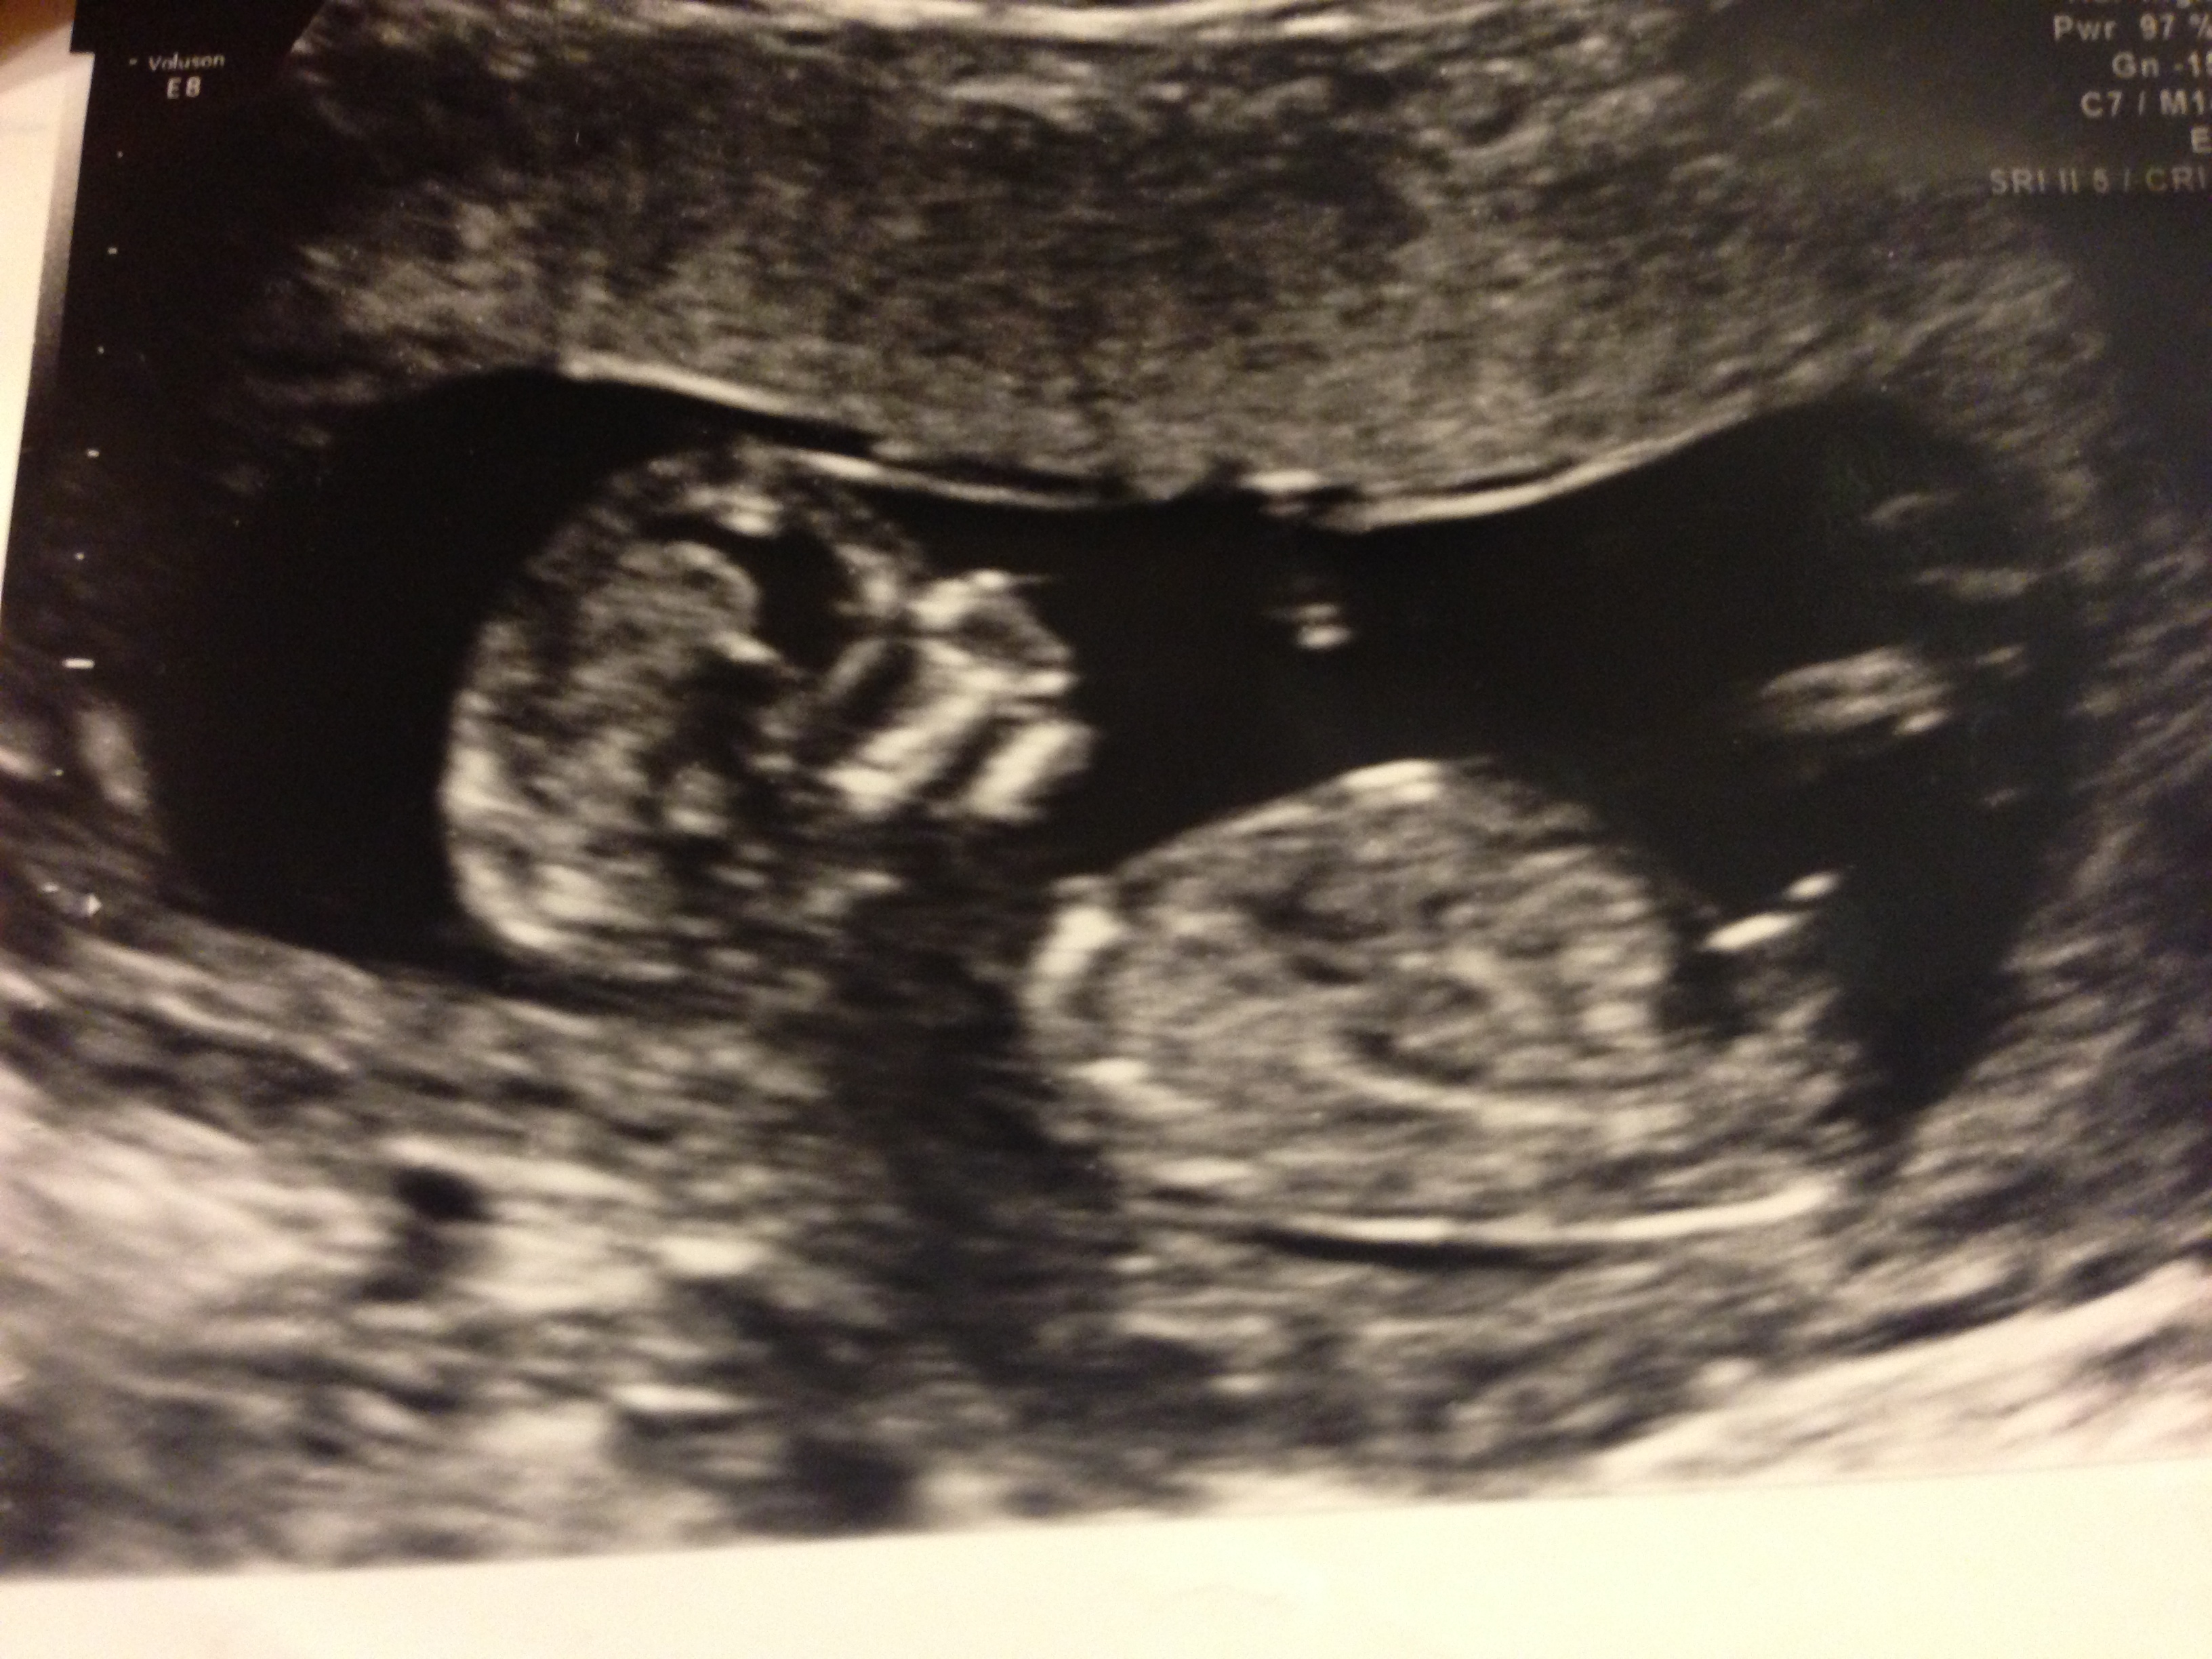

Boy :) Nub looks like it is pointing upwards and skull theory looks boy. Congrats!

I'm thinking boy :)

If that is the nub (I can't tell for sure) then I guess boy too!